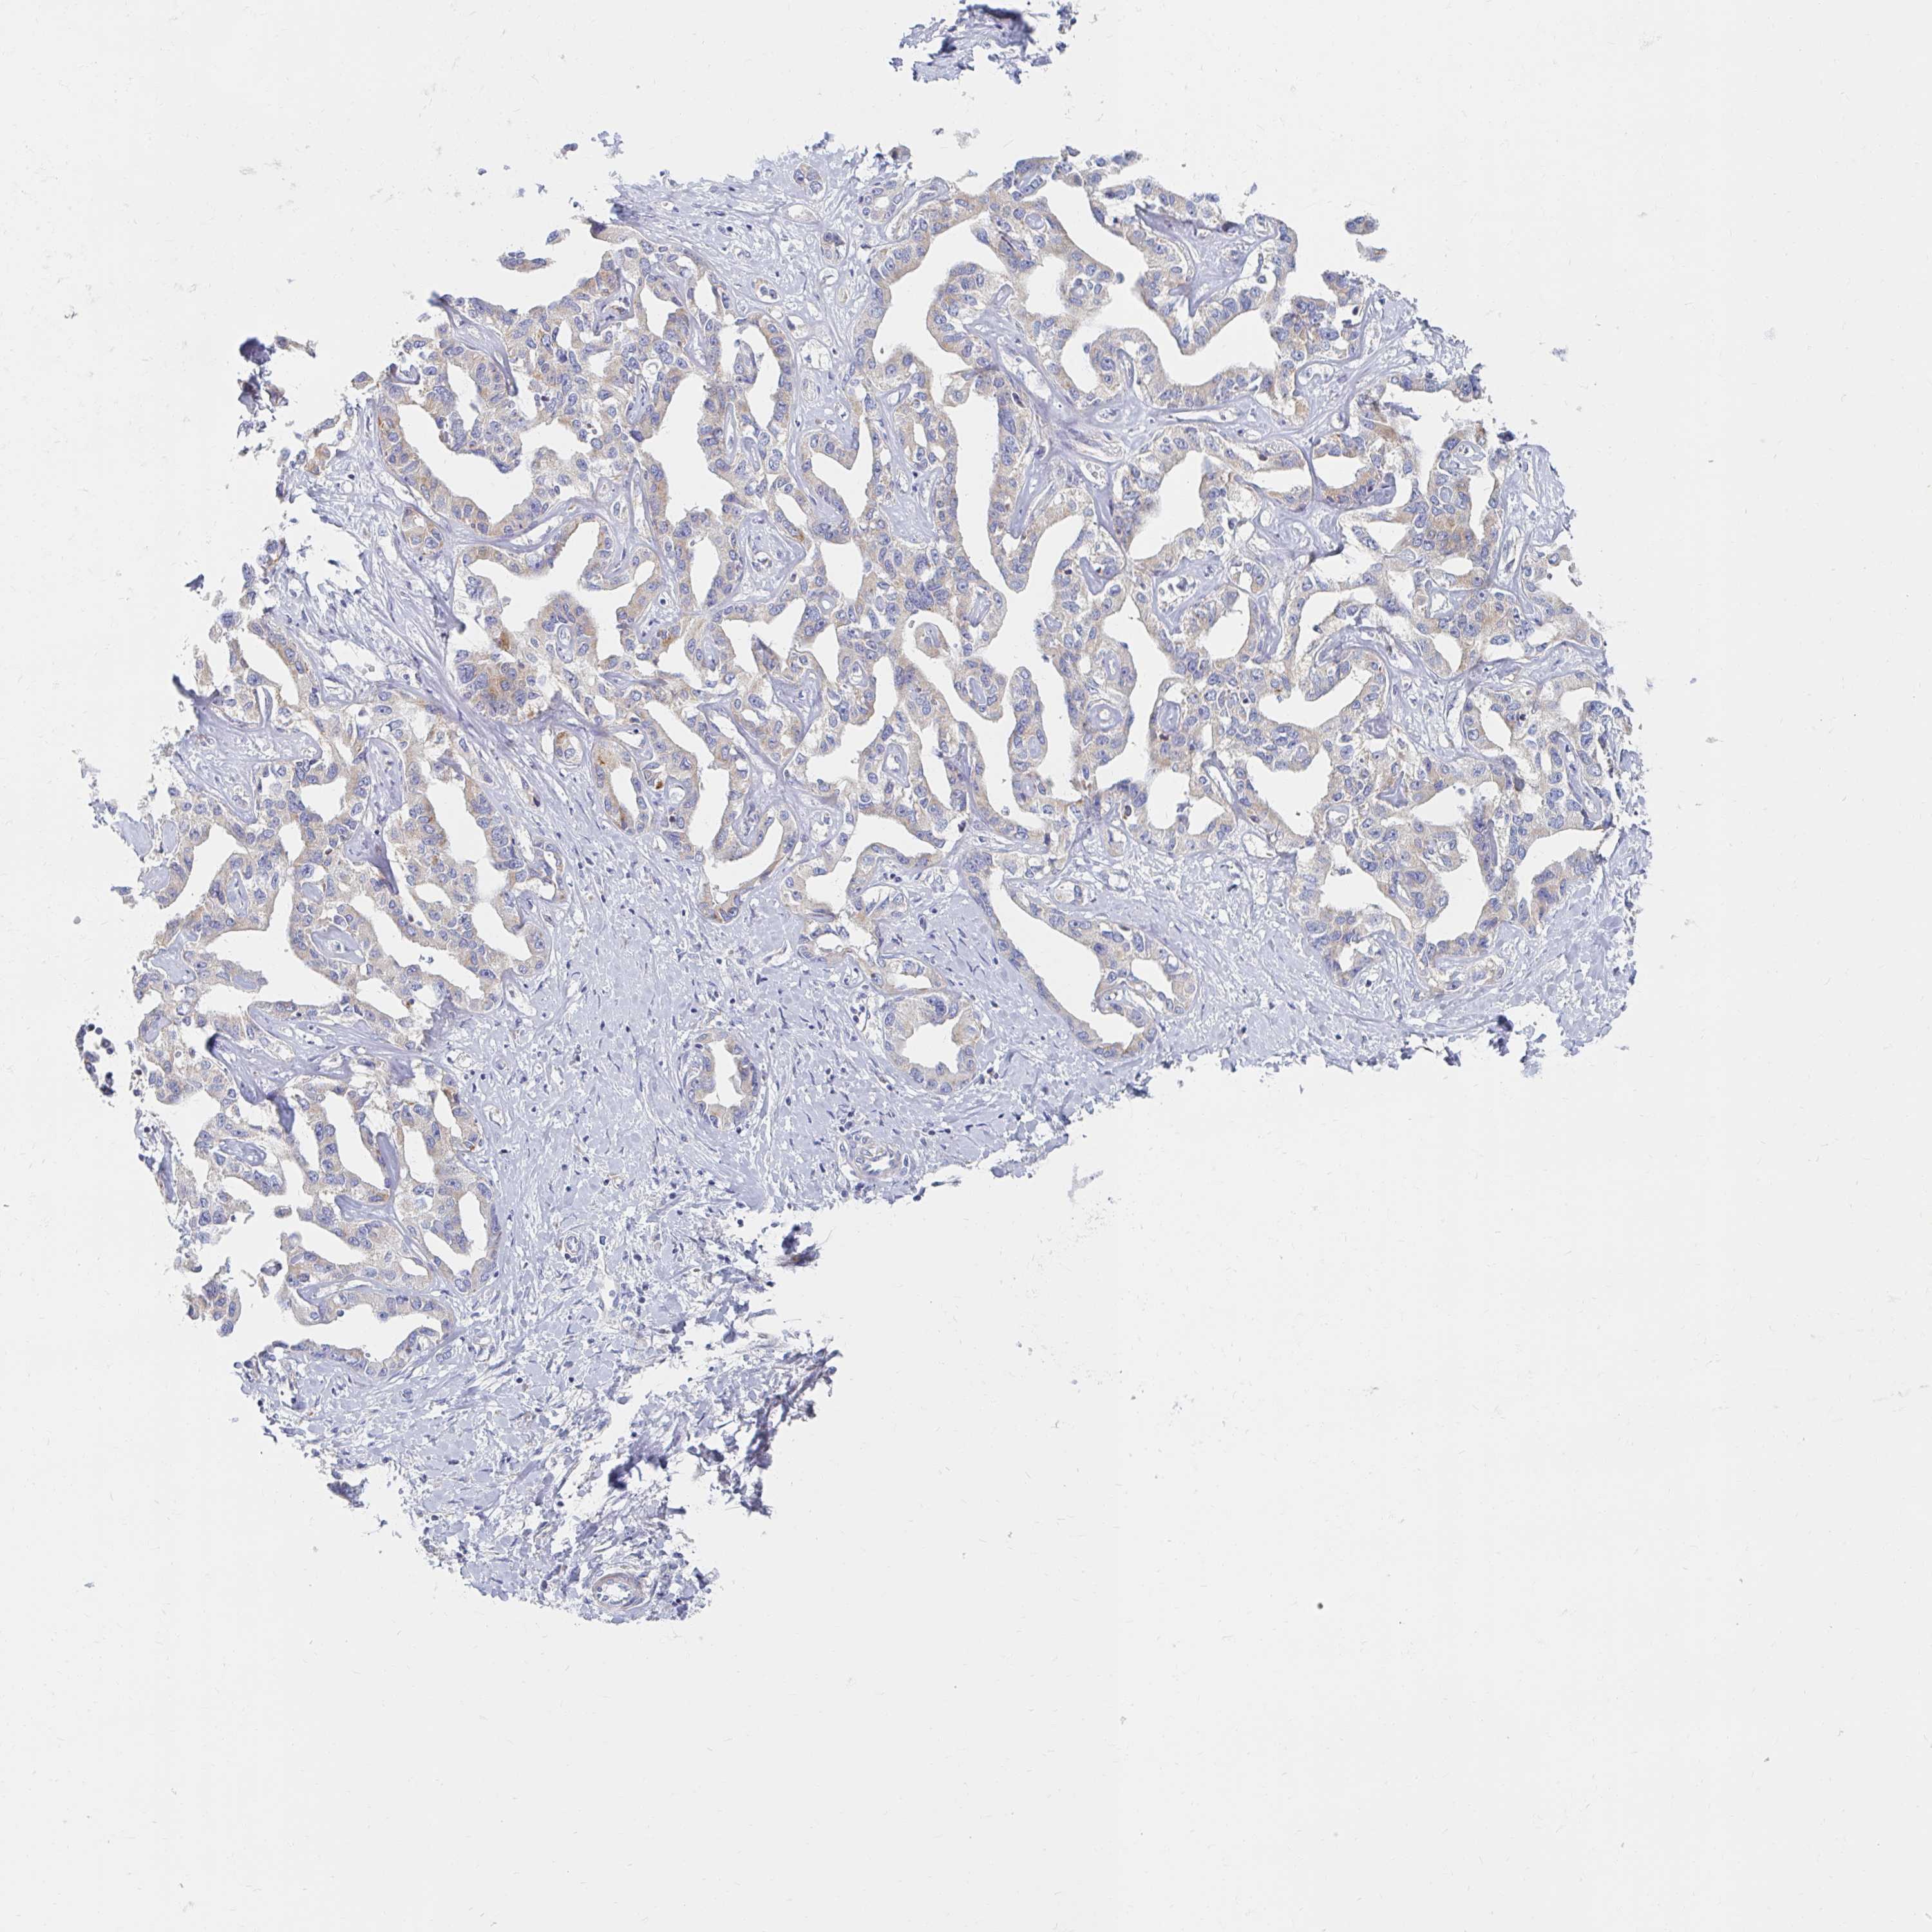

LIVER CANCER - Protein expressioni

A mouse-over function shows sample information and annotation data. Click on an image to view it in a full screen mode. Samples can be filtered based on level of antibody staining by selecting one or several of the following categories: high, medium, low and not detected. The assay and annotation is described here.

Note that samples used for immunohistochemistry by the Human Protein Atlas do not correspond to samples in the TCGA dataset.

Antibody stainingi

Antibody staining in the annotated cell types in the current human tissue is reported as not detected, low, medium, or high, based on conventional immunohistochemistry profiling in selected tissues. This score is based on the combination of the staining intensity and fraction of stained cells.

Each image is clickable and will lead to virtual microscopy that enables deeper exploration of all samples and also displays staining intensity scores, fraction scores and subcellular localization as well as patient and tissue information for each sample.

Antibody HPA049850

Antibody HPA053524

Antibody CAB009187

Staining

High

Medium

Low

Not detected

Intensity

Strong

Moderate

Weak

Negative

Quantity

>75%

75%-25%

<25%

None

Location

Nuclear

Cytoplasmic/membranous

Cytoplasmic/membranous,nuclear

Carcinoma, Hepatocellular, NOS

Cholangiocarcinoma